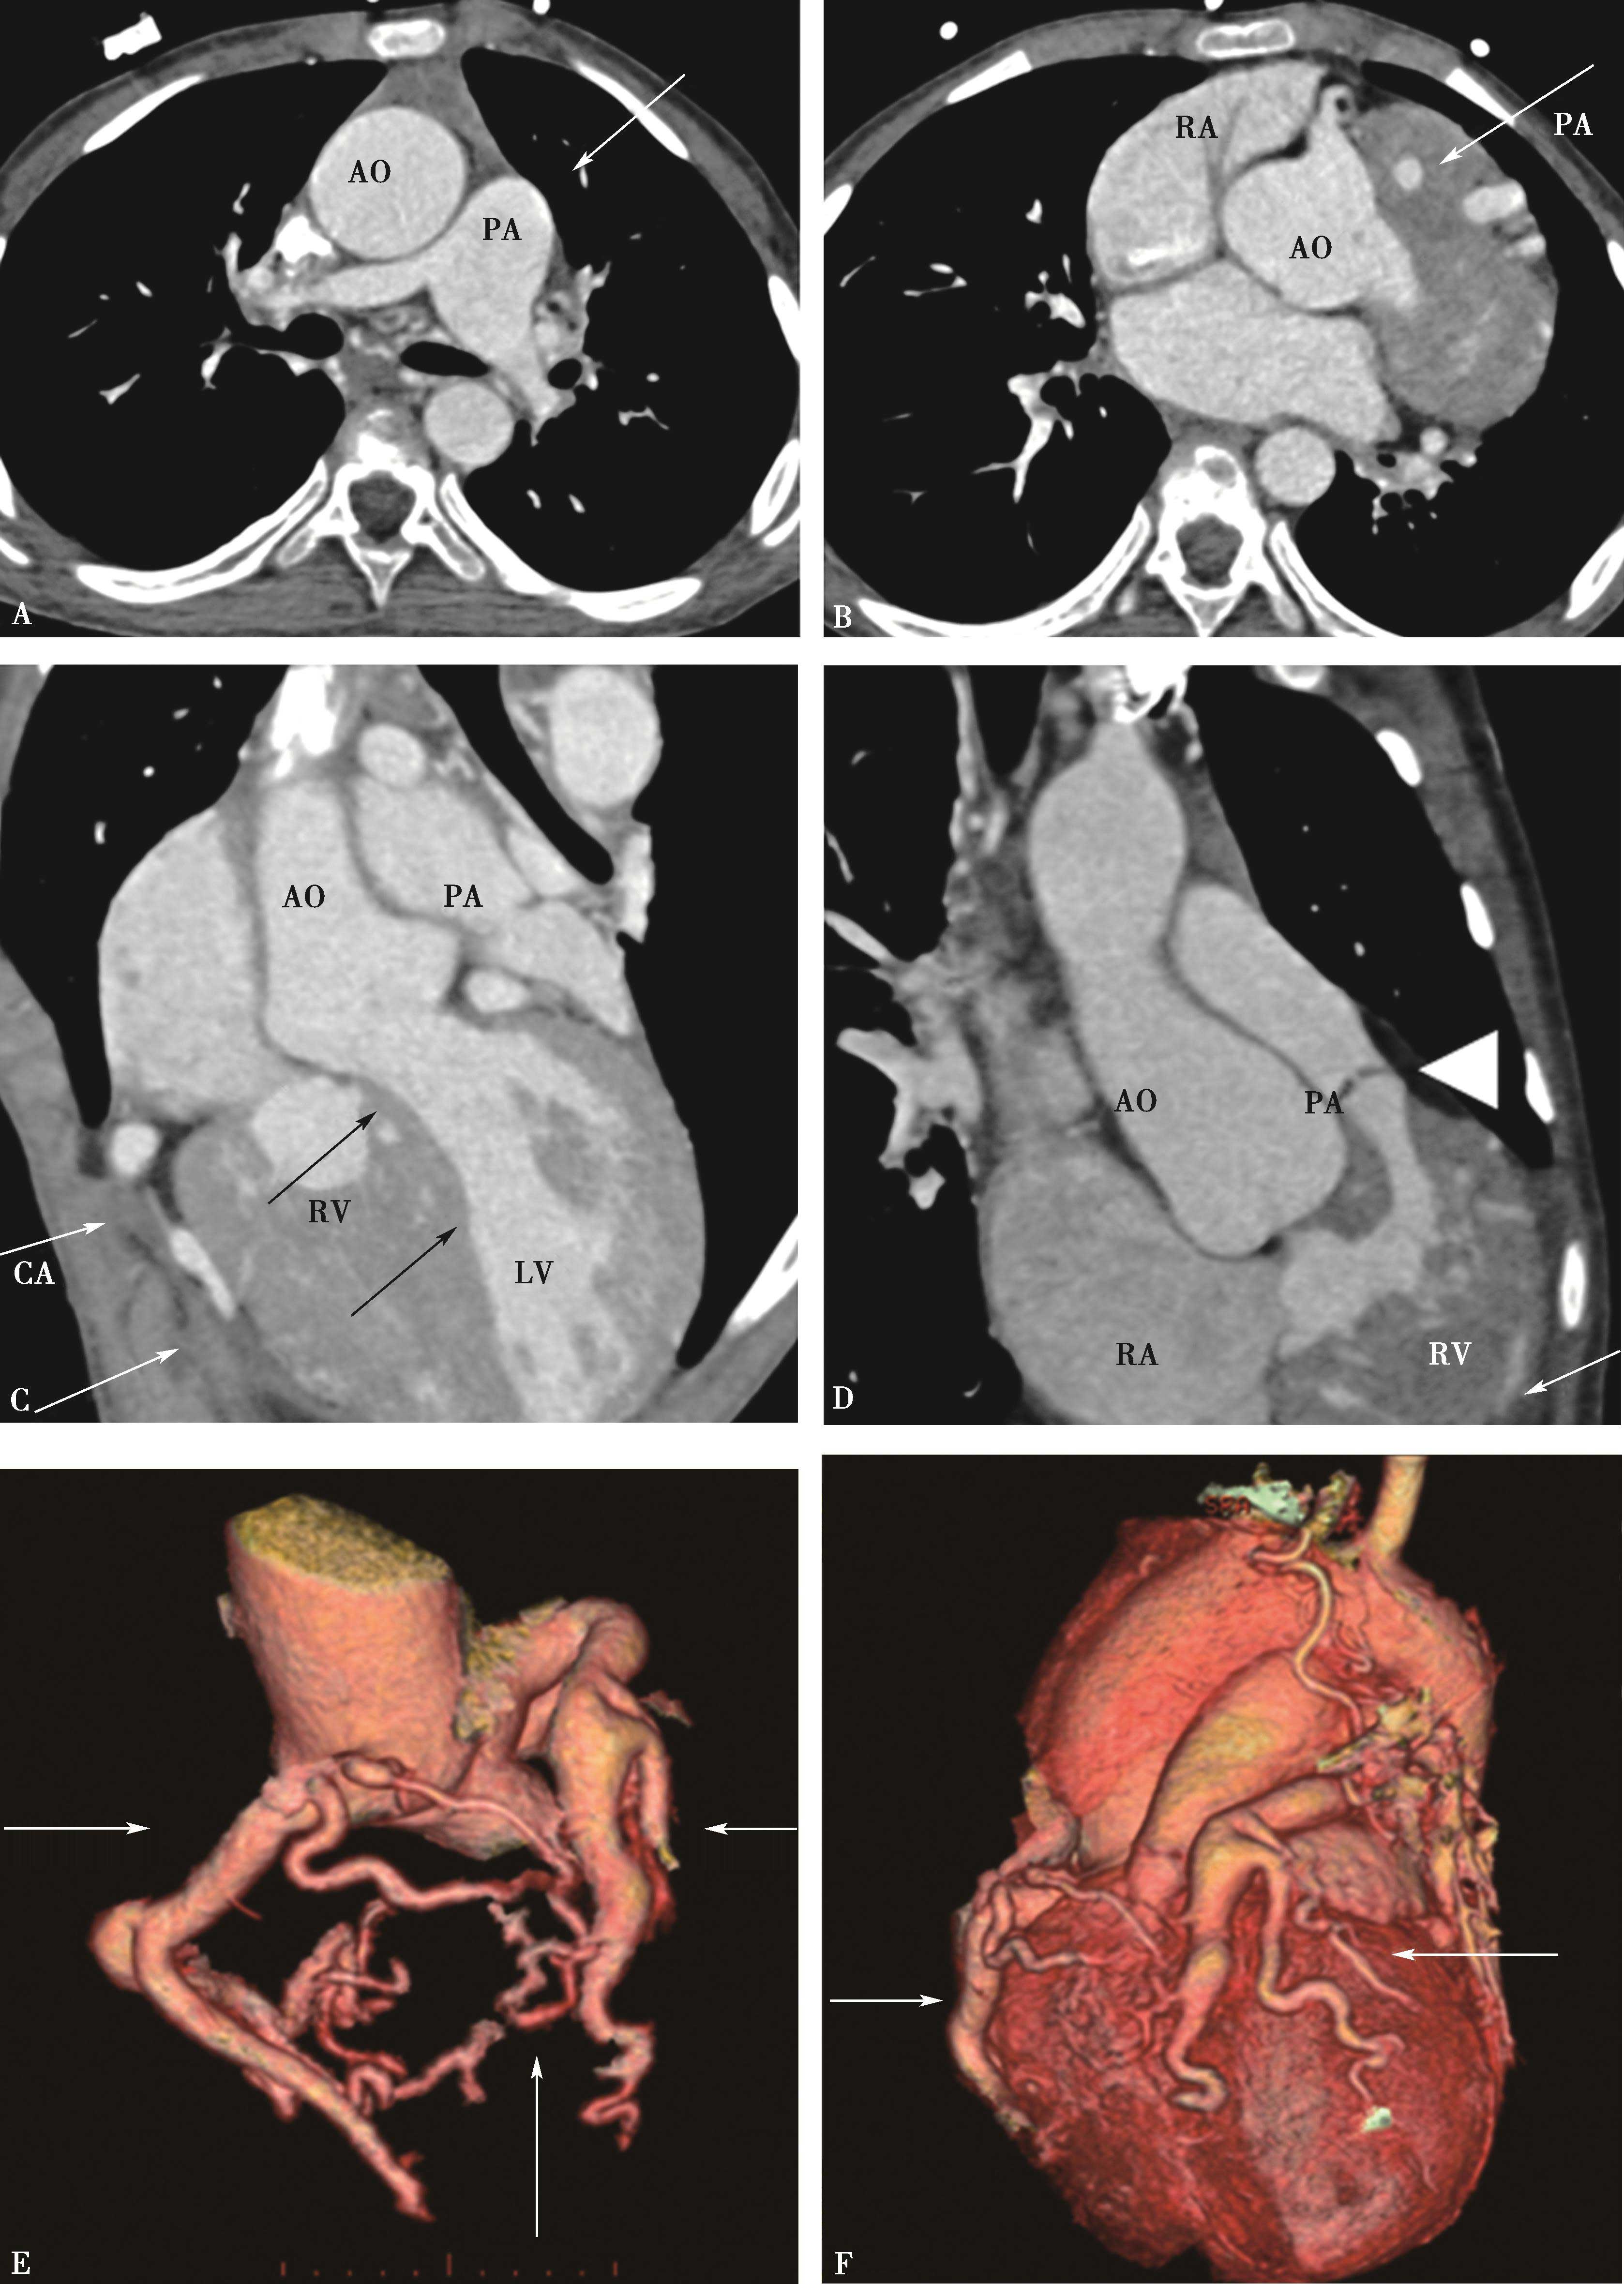

容积再现技术的优点是:①可以直观地反映物体的空间位置、结构和与其他器官的关系,是真正的三维立体重建;②容积再现技术保留了原始数据的全部信息,可以直接对图像进行分析处理,直接从立体图像上进行原始数据提取和测量,增强了交互性。对肺动脉及肺静脉疾患诊断有重要价值(图8-2-1)。

图8-2-1 肺动脉容积再现(VR)

正常肺动脉:A.冠状位;B.背面观;C.左前斜位;D.右前斜位

3.容积再现(VR)(图8-2-9)

图8-2-9 肺动脉容积再现与肺动脉DSA对照图

肺动脉DSA(ACE):A.肺动脉DSA(冠状位);C.右肺动脉DSA(矢状位);E.左肺动脉DSA(矢状位)。肺动脉容积再现(BDF):B.肺动脉VR(冠状位),D.右肺动脉VR(矢状位),F.左肺动脉VR(矢状位)。上叶:1.尖段;2.后段;3.前段。(右肺)中叶:4.外侧段;5.内侧段。(左肺)舌叶:4.上舌段;5.下舌段。下叶:6.背段;7.内基底段;8.前基底段;9.外基底段;10.后基底段